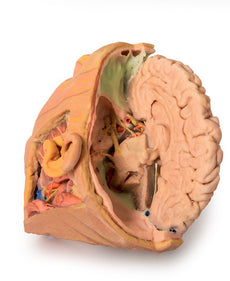

The head and neck of the specimen provides views of both superficial and deep structures in the region. The calotte has been removed ~2cm superior to the orbits to expose the brain in relation to the endocranial cavity. The transverse section through the cerebrum demonstrates the relation of the grey matter cortex to the white matter medulla, as well as the lateral ventricles with a small amount of choroid plexus visible in the base of both spaces. The skin and superficial fascia on the right side has been retained and false-coloured to display the angiosomes of the face and posterior neck. On the left side, the superficial tissues have been dissected to expose the muscles of facial expression, muscles of mastication, and deeper structures of the infratemporal fossa including the lingual nerve, terminal branches of the external carotid artery into the superficial temporal and maxillary arteries.

The head and neck of the specimen provides views of both superficial and deep structures in the region. The calotte has been removed ~2cm superior to the orbits to expose the brain in relation to the endocranial cavity. The transverse section through the cerebrum demonstrates the relation of the grey matter cortex to the white matter medulla, as well as the lateral ventricles with a small amount of choroid plexus visible in the base of both spaces. The skin and superficial fascia on the right side has been retained and false-coloured to display the angiosomes of the face and posterior neck. On the left side, the superficial tissues have been dissected to expose the muscles of facial expression, muscles of mastication, and deeper structures of the infratemporal fossa including the lingual nerve, terminal branches of the external carotid artery into the superficial temporal and maxillary arteries.